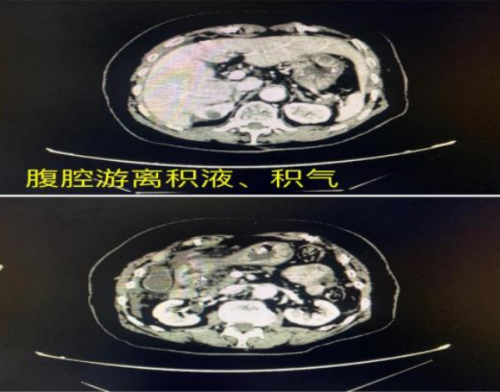

“患者入院时上腹部疼痛剧烈,呈刀割样、持续性,查体发现全腹肌紧张,全腹压痛、反跳痛,肠鸣音消失,胸腹部CT提示:腹腔游离积液、积气,考虑上消化道穿孔,穿孔点考虑位于胃窦部、十二指肠球部水平。”据急诊科副主任邵启兵介绍,病情紧急,立博体育 马上开通绿色通道,在全麻下行腹腔镜胃窦穿孔修补+肠粘连松解术,术程顺利,术后转入急诊ICU严密监护治疗,经过精心治疗和护理,患者病情趋于平稳,于术后第2天停用呼吸机拔除气管插管,转入普通病房。